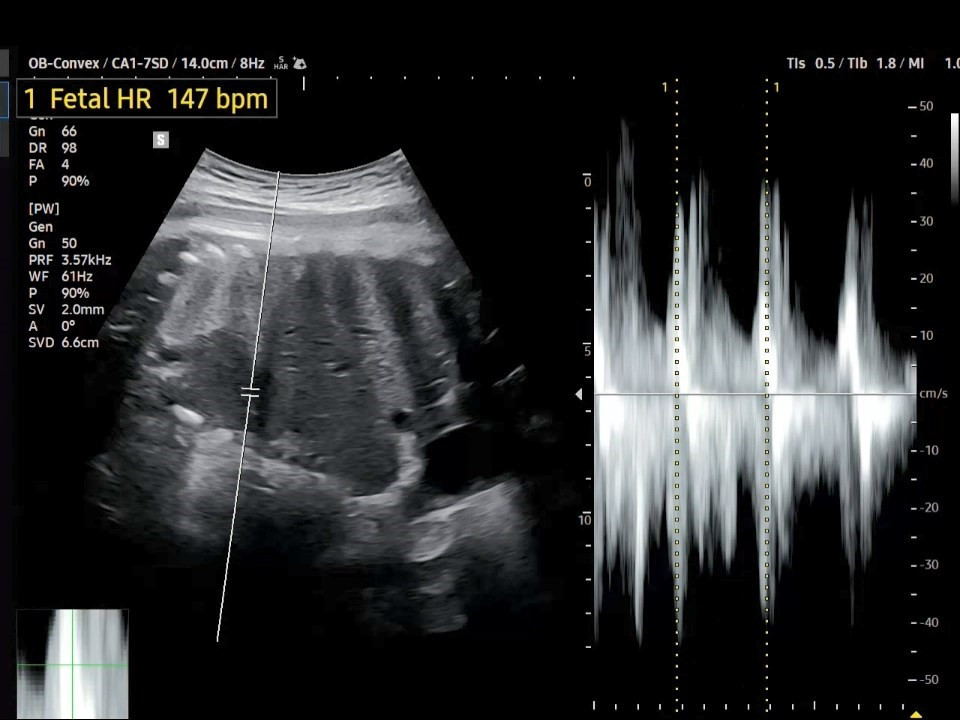

1. 심장박동수(Fetal Heart Rate)는 지난번 37주 차의 FHR과 동일하게 147 bpm입니다.

38주 FHR.jpg [38주 차 심장박동수]